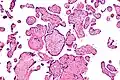

Histomorphologically, VUE is characterized by a lymphocytic infiltrate of the chorionic villi without a demonstrable cause. Plasma cells should be absent; the presence of plasma cells suggests an infective etiology, e.g. CMV infection.

Intermed. mag.

High mag.